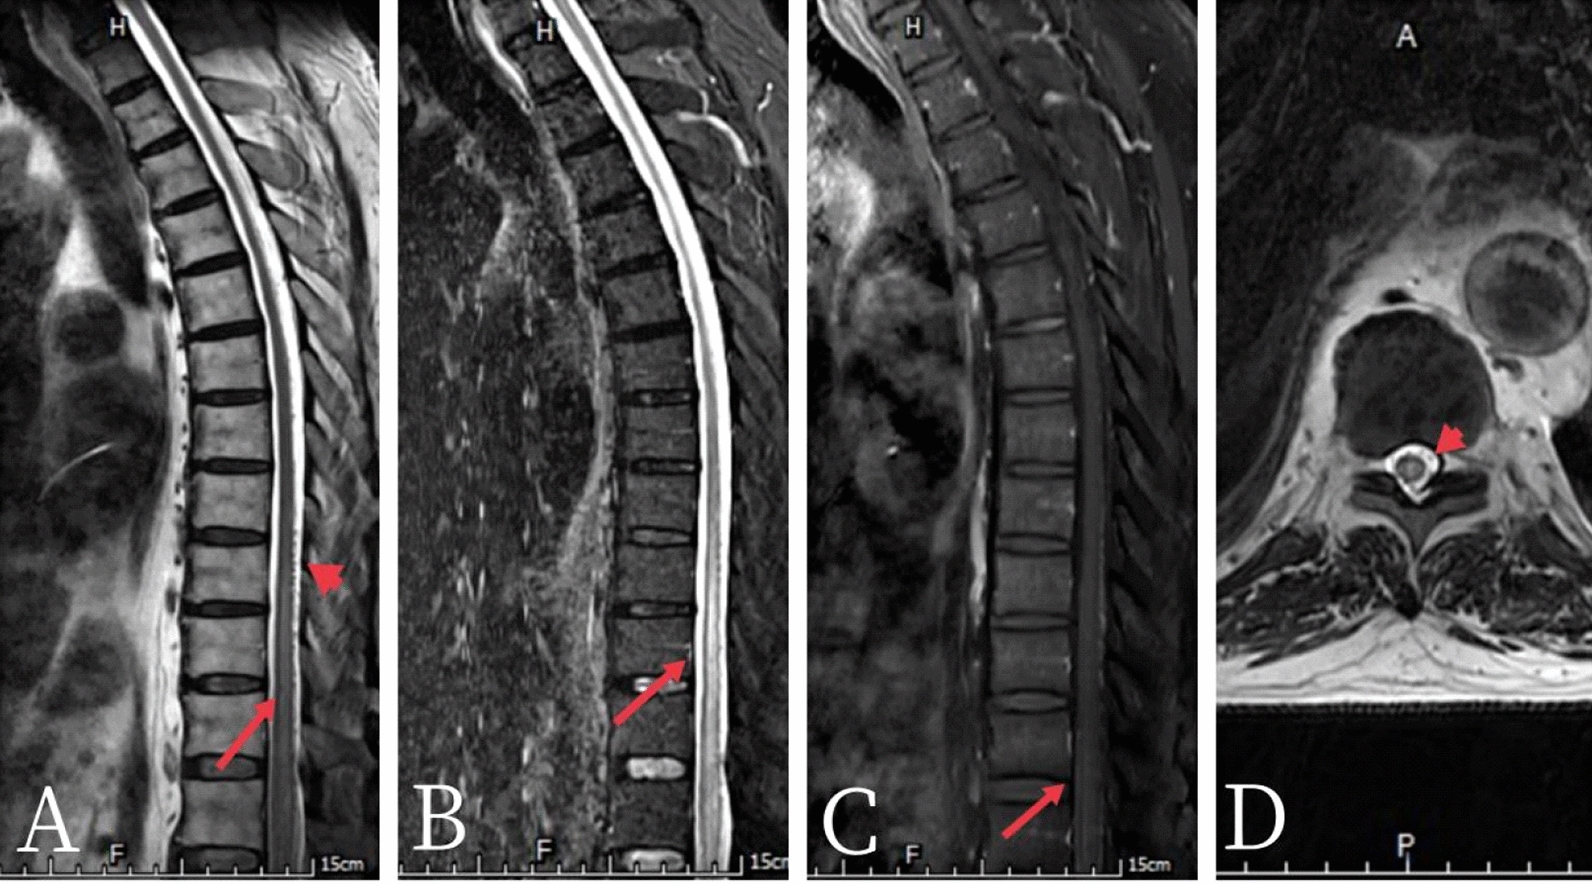

Case presentation: A 76-year-old Chinese male patient presented with numbness and weakness of the lower limbs that rapidly progressed to complete paralysis within 4 days. Patient was diagnosed with spinal dural arteriovenous fistula after magnetic resonance imaging and spinal vascular angiography, undergoing bilateral internal iliac artery embolization 2 weeks later, and started rehabilitation 40 days later but only received minimal improvement 1 year thereafter.